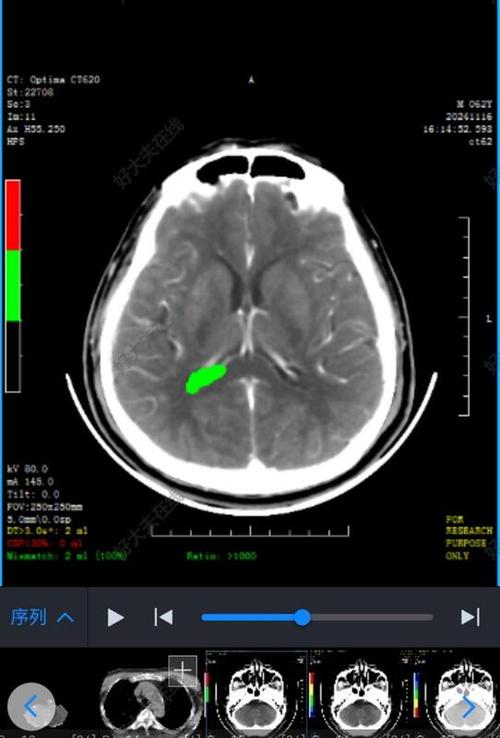

亚急性期(发病3天 - 2周)—— CT表现最典型

这是CT诊断脑梗的“黄金时期”,脑组织水肿达到顶峰,坏死区域变得非常清晰。

- CT表现:

- 明显的低密度灶: 梗死区域在CT上呈现为边界清晰、形态与相应供血动脉分布一致的低密度影,这是脑梗在CT上最典型的表现。

- 占位效应: 严重的水肿会导致脑组织受压,中线结构(如大脑镰)移位,这是判断病情严重程度的重要指标。